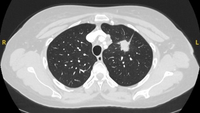

Computed tomography (CT) section with soft tissue configuration, showing a right lung hamartoma, as incidental finding in an asymptomatic patient. Note the central calcification and several small spots of fat within the nodule. This nodule was stable over a 12 year period and no intervention required

From the collection of Dr George Tsaknis, MD, PhD, FRCP(London), MRQA, MAcadMEd, PGCert; used with permission